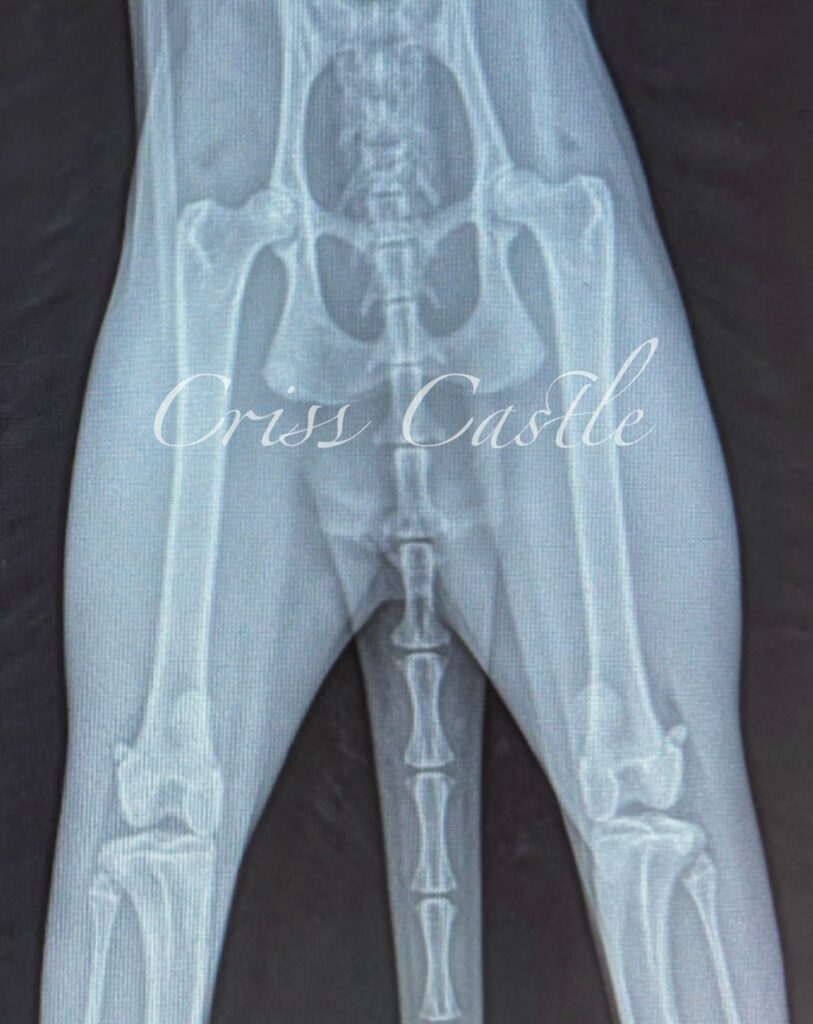

Hip X-Ray Results

Below are the current hip x-ray results for each Criss Castle breeding cat.

Note that as the cats continue to grow, this page may be updated with new results.